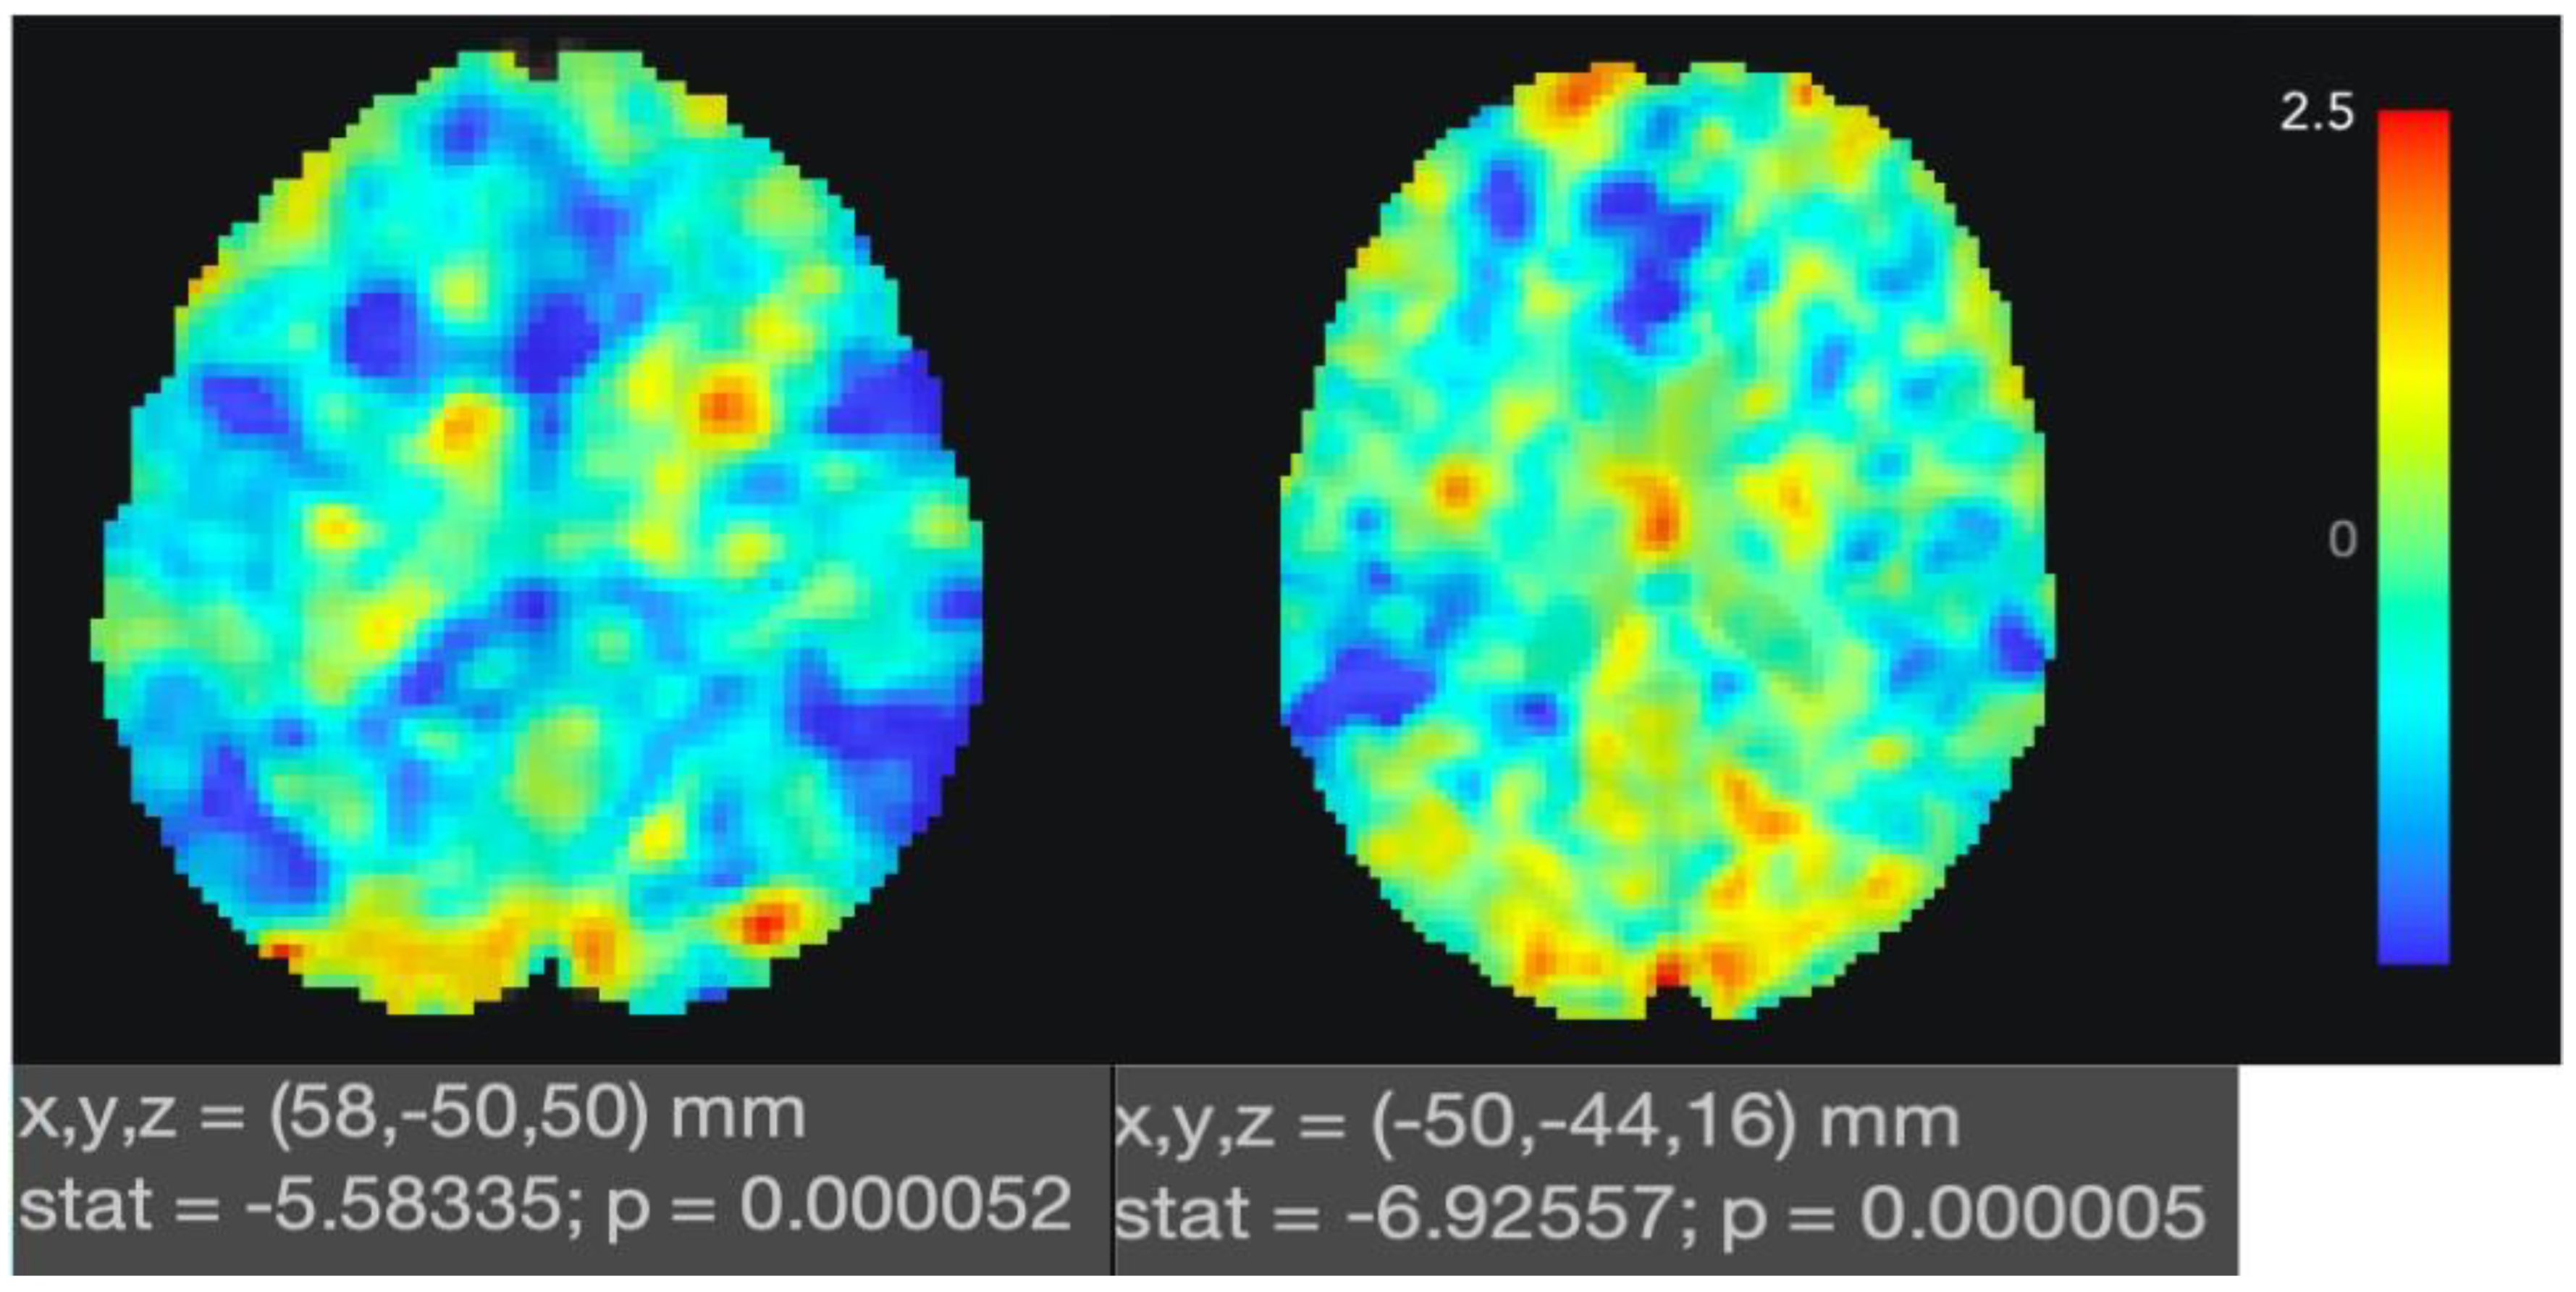

| Brain Region | MNI Coordinates | Cluster Size | t-Value | ||

|---|---|---|---|---|---|

| x | y | z | |||

| Supramarginal gyrus (posterior right) | 58 | −50 | 50 | 85 | −5.58 |

| Supramarginal gyrus (posterior left) | −50 | −46 | 16 | 86 | −7.97 |